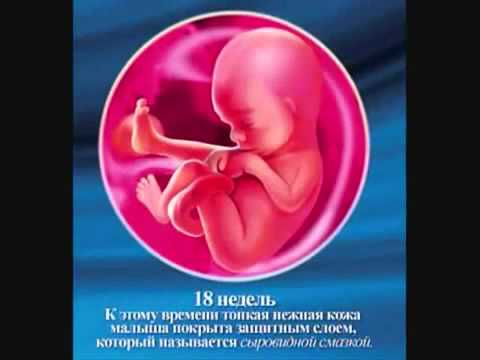

Плід на 21 тижні вагітності виріс приблизно до 20 -25 сантиметрів і важить 360 -400грамм. Його травна система все більше вдосконалюється, захоплюючи амніотичну рідину, малюк тренує свій стравохід і легені. На цьому терміні можна сформувати смакові пристрасті малюка.

Працює ендокринна система, підключається до роботи і селезінка. Іноді дитина дуже активний ночами, і якщо заспівати колискову пісеньку, він засне. Дітки здатні реагувати на настрій мами і на її голос.

Розмір плоду вже становить 18 см, а вага дитини досягає 350 грам. Матка подннімается над пупком приблизно на 1 см.

Дитина активно розвивається і росте, накопичуючи підшкірні жири. Малюк здатний здійснювати глотки, на його мові формуються смакові закінчення.

У дитини формується режим дня: він то спить, то не спить. Малюкові вільно в животику, що росте з кожним днем.

Хребет вже накопичує кальцій і стає твердим, розвивається координація рухів і сила м'язів.